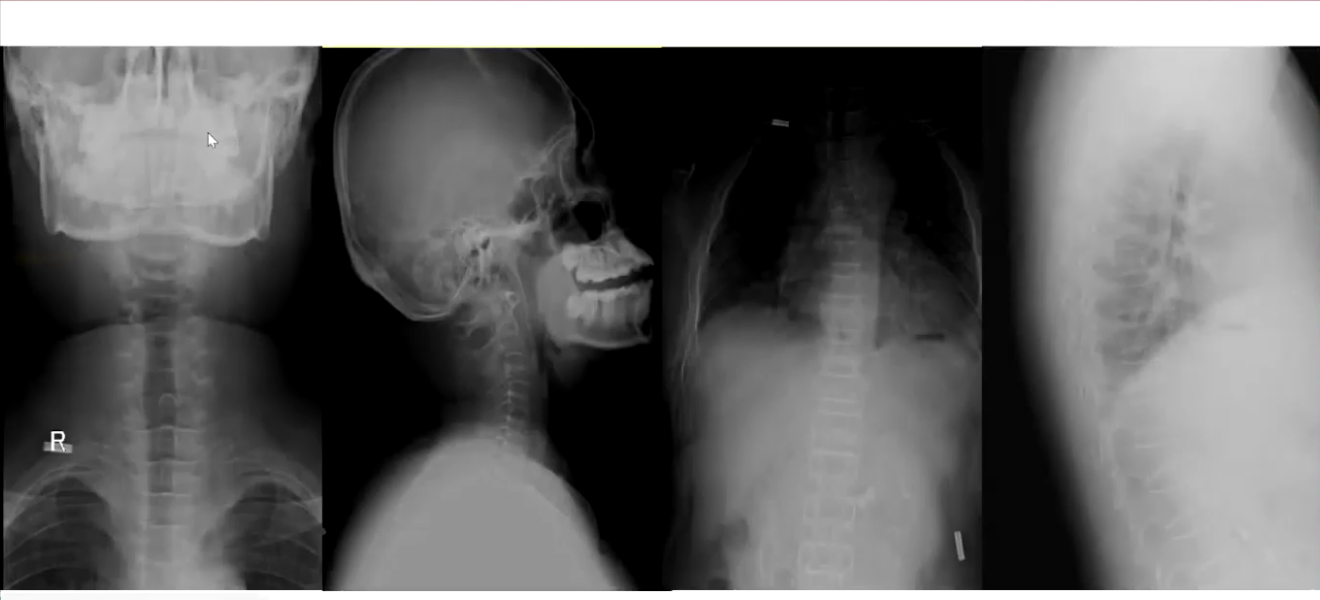

X线:骨密度检查提示严重骨质疏松;立位腹平片、腰椎平片及头颅平片显示骨骺线几乎闭合,颈腰椎及骨盆骨质疏松,胸腰椎椎体楔形变。